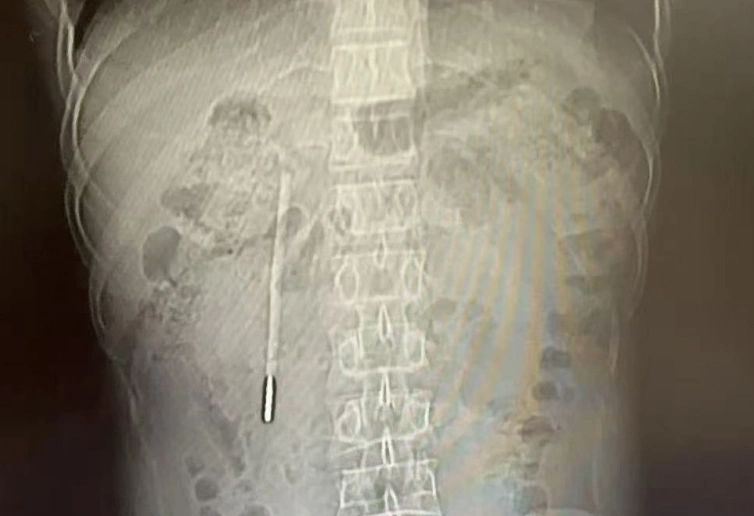

An X-ray showing a mercury thermometer inside the patient's abdomen. Photo: Wenzhou Metropolitan Daily |

Chinese media reported that Wang, 32, sought medical attention due to persistent bloating and indigestion. A computed tomography (CT) scan of his abdomen revealed a foreign object in his duodenum, identified as a mercury thermometer. The sharp tip of the thermometer was pressing against the intestinal wall, threatening to cause perforation or severe bleeding at any moment.